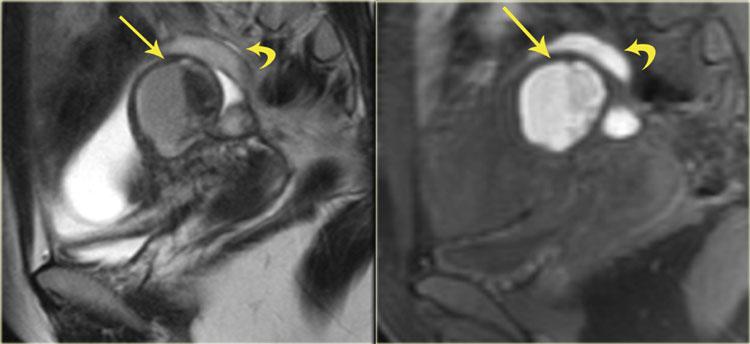

Hình ảnh chuỗi xung T2 và T1 xóa mỡ của nang lạc nội mạc tử cung với giảm tín hiệu trên T2 (hiệu ứng shading), mức dịch-dịch trên T2 (trái) và máu tăng tín hiệu trên chuỗi xung T1W có xóa mỡ (phải).

Trên MRI, nang lạc nội mạc tử cung biểu hiện là các khối đơn độc hoặc đa ổ với tín hiệu tăng đồng nhất trên chuỗi xung T1 và T1 xóa mỡ.

Chuỗi xung T1 xóa mỡ giúp phân biệt nang lạc nội mạc tử cung với u quái dạng nang trưởng thành, thường chứa mỡ.

Trên chuỗi xung T2W, nang lạc nội mạc tử cung có thể có tín hiệu từ giảm tín hiệu (còn gọi là hiệu ứng shading) đến tín hiệu trung gian hoặc tăng tín hiệu.

Tín hiệu thấp phản ánh tình trạng cô đặc máu trong nang.

Nang lạc nội mạc tử cung thường có vỏ xơ dày với giảm tín hiệu trên T2, do các đại thực bào chứa hemosiderin gây ra (hình minh họa).

Bên trái là một ví dụ khác về nang lạc nội mạc tử cung.

Hình ảnh chuỗi xung T2 và T1 xóa mỡ cho thấy một nang có cục máu đông (giảm tín hiệu trên T2, tín hiệu trung gian trên T1).

Đôi khi các cục máu đông này đi kèm với mô xơ trên mô bệnh học.

Chúng có thể được nhận biết là các tổn thương giảm tín hiệu (trên T2) có hình dạng bất thường, nằm ở phần thấp nhất của nang lạc nội mạc tử cung.

Trong trường hợp này còn có hình ảnh ứ máu vòi trứng (mũi tên cong).